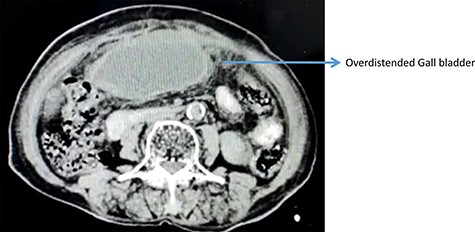

On computerized tomography, there was no additional finding (Fig. 2).

Contrast enhanced computed tomography abdomen showing over distended GB.